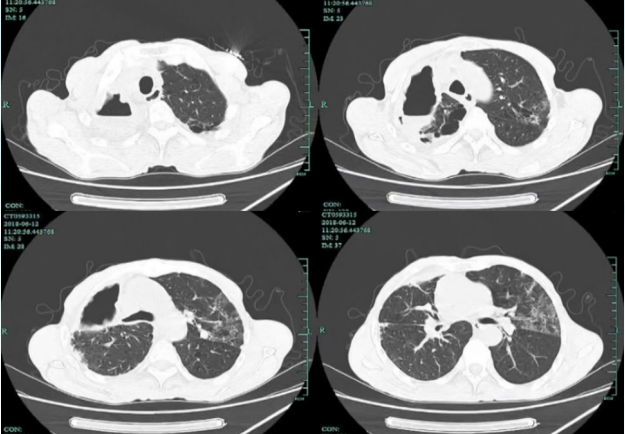

通常EBV放置6~8周后需取出,如放置时间过长,可能出现肉芽组织增生,取出时可能发生明显出血。于是在7月10日取出EBV。7月11日复查胸部CT可见较前明显好转,中叶复张,无感染病灶11。基本治愈。

图片

11  复查胸部CT